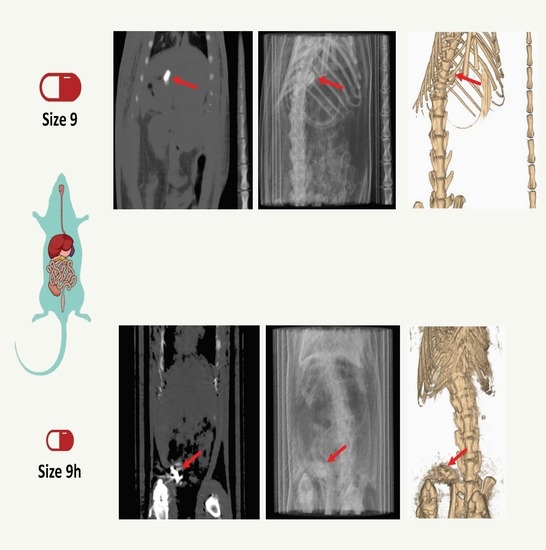

3. Results and Discussion